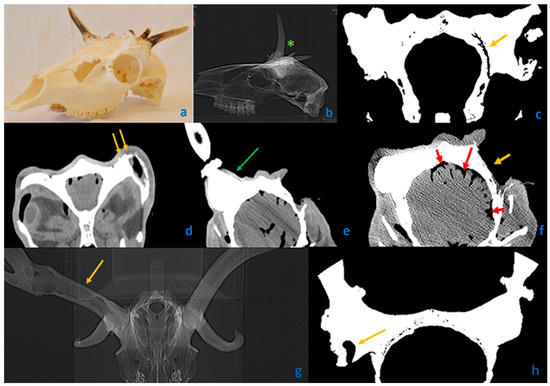

3.3. Characteristics of Fallow Deer (Dama dama) Aberrant Trophies

3.4. Antler Anomalies in Roe Deer (Capreolus capreolus) Trophies

3.5. Occurrence of RAPS Features in Red Deer (Cervus elaphus)

3.9. Peduncular–Dermal Junction (PDJ); Structural and Pathological Insights